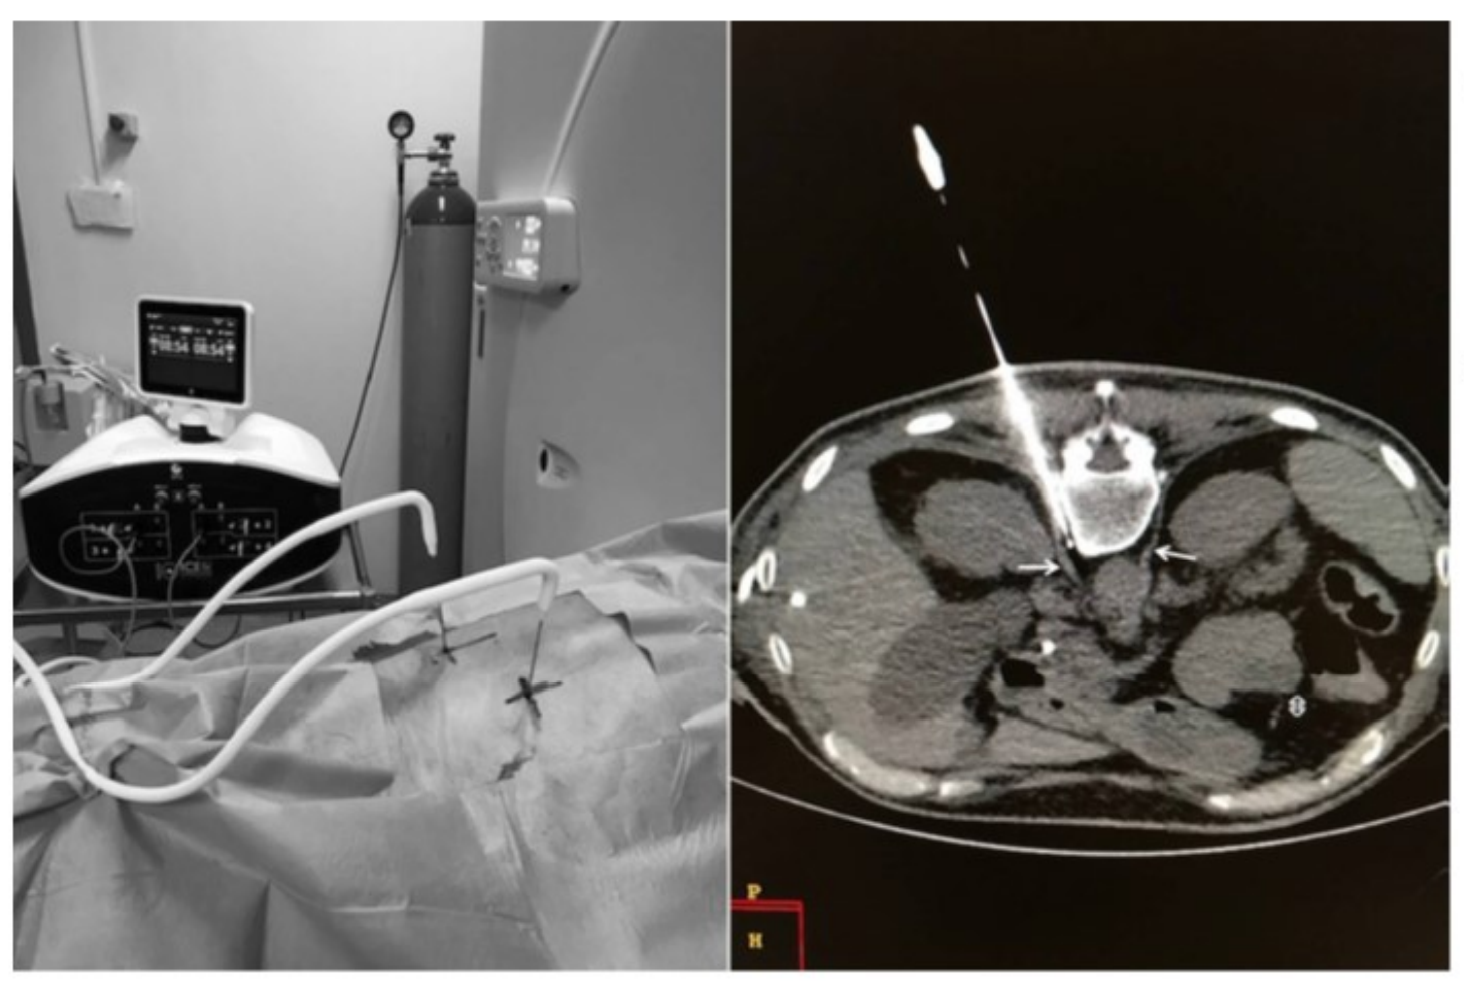

Криоанальгезия межреберных нервов

• N=18. Интенсивность боли: 7.5 баллов исходная, 1,2 после процедуры и 4.1 балла через 51 день. W. Moore, D. Kolnick, J. Tan, H.S. Yu. CT guided percutaneous cryoneurolysis for post thoracotomy pain syndrome: early experience and effectiveness. Acad Radiol. 2010 May;17(5):603-6.

• N=43 (ретроспективное). 60% значимое снижение боли после процедуры, 50% значимое снижение боли через 3 мес. Не было невром, невритов и только 3 случая пневмоторакса.

C.R Green, A.M. de Rosayro, A.R. Tait. The role of cryoanalgesia for chronic thoracic pain: results of a long-term follow up. J Natl Med Assoc. 2002 Aug;94(8):716-20.

Лечение онкологической боли

• N=5. Интенсивность боли у пациентов с раком ПЖ снизилась с 9.4 ВАШ до 2.6, 2.6 и 3 через 1, 3 и 6 мес.

• D. Filippiadis, N. Ptohis, E. Efthymiou, A. Kelekis. A Technical Report on the Performance of Percutaneous Cryoneurolysis of Splanchnic Nerves for the Treatment of Refractory Abdominal Pain in Patients with Pancreatic Cancer: Initial Experience. Cardiovasc Intervent Radiol (2021) 44:789-794.

Криоанальгезия при онкологической боли